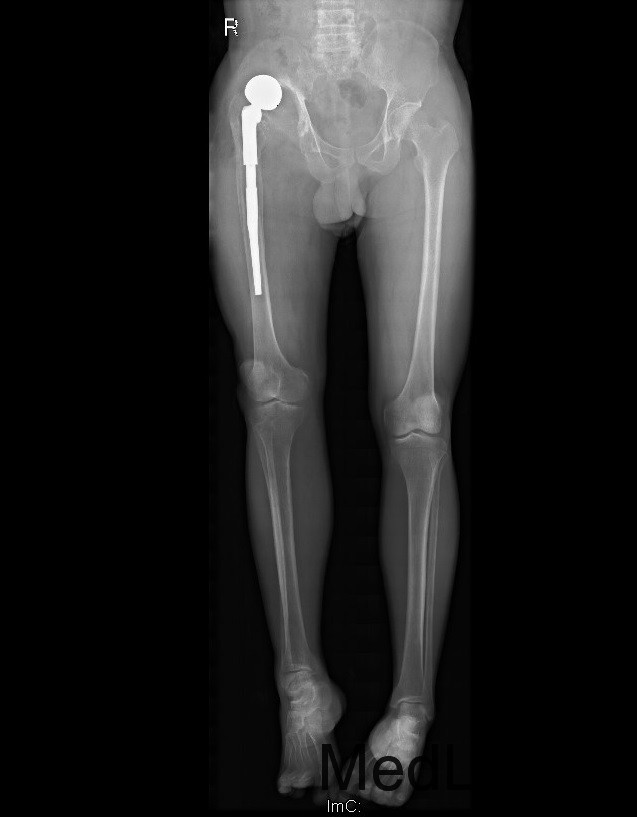

查体:右髋关节前方可见约13X2CM、后外侧可见约23X1CM手术切口瘢痕。右下肢短缩。双侧髋关节周围皮温正常,温、痛觉灵敏。局部软组织柔软。双侧髋关节周围无压痛,被动屈伸、内外旋及内收外展可,无内外旋诱发痛。双下肢足背动脉搏动正常。右髋后方较左侧松弛,可触及股骨头。右下肢短缩5cm。右髋关节屈120度,伸0度,内外旋40°,外展30度,内收20度。左髋关节屈130度,伸0度,内外旋40°,外展30度,内收20度。右下肢外展肌力3级。双下肢无轴向叩击痛。双侧直腿抬高试验(-),双膝、双踝关节活动正常。 辅助检查:X线;05年10月 示右股骨头变形,右髋关节间隙变窄。05年11月 右股骨头塌陷,关节间隙变窄,右髋关节腔周围可见游离骨块。05年11月,右股骨头消失,右髋关节腔内游离骨块 05年12月,右股骨头缺如,右股骨颈上段部分缺失,右髋关节腔内游离骨块减少。06年3月,右股骨颈进一步缺失,大转子上移,臼缘骨质增生。06年7月,右全髋置换术后,06年11月示右髋置换术后假体位置尚可,07年8月示髋臼假体移位,股骨柄下沉,股骨上段皮质增生,可见骨膜反应。07年11及12月,可见髋臼及股骨柄周围骨溶解,假体松动,人工关节脱位。08年1月及4月 右髋临时骨水泥假体固定术后松动移位,髋臼及股骨侧骨溶解。08年9月示右髋二期翻修术后,假体位置良好。08年12月 部分右髋臼螺钉松动,臼杯松动,09年2月示部分右髋臼螺钉断裂,臼杯松动,03年3月大量右髋臼螺钉断裂,臼杯明显移位,外移、右髋脱位。09年9月及12月见臼杯破裂。

诊断:1、右髋结核病灶清除术后右全髋置换术后感染翻修术后假体松动、髋关节脱位、髋臼骨缺损。(AAOS III型)右下肢短缩。2、右髋Charcot 关节病? 治疗:右髋关节置换术后右股骨头假体取出、右髋臼骨缺损结构骨移植、颗粒骨打压植骨,cage、加强环骨水泥髋臼重建,股骨端假体颈延长、股骨头置换术。